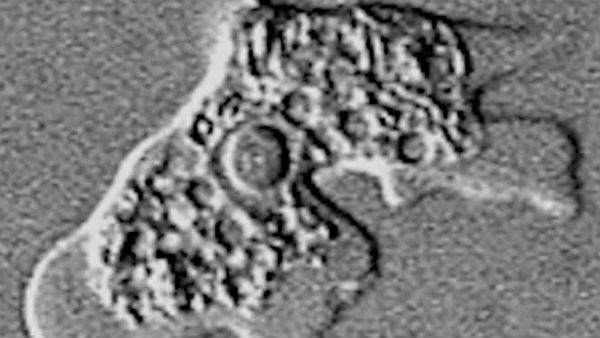

నయేగ్లేరియా ఫోలేరీ అనే ఈ అమీబా నాసిక రంధ్రాల ద్వారా శరీరంలోకి ప్రవేశించి మెదడు వరకు పాకుతుందని వైద్య నిఫుణులు చెబుతున్నారు. మెదడులో టిష్యూను ధ్వంసం చేస్తుందని వారు చెప్పారు. 2009 నుంచి 2018లో ఈ అమీబా బారిన పడిన వారి సంఖ్య 34గా ఉన్నిందని చెప్పారు. 1962 నుంచి 2018వరకు ఈ తరహా అమీబా బారన పడిన వారు కేవలం నలుగురు మాత్రమే బతికినట్లు వైద్యులు చెబుతున్నారు.